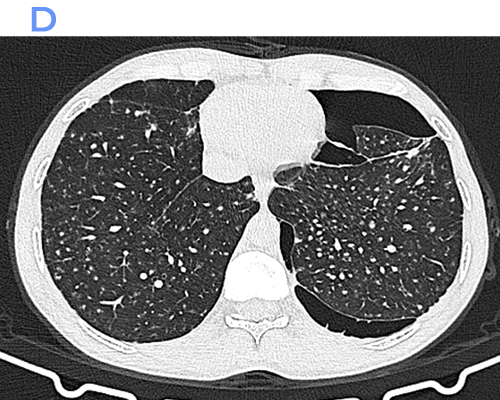

Computed Tomography (CT)

• Numerous well-defined centrilobular and perilymphatic nodules in the upper lobes.

• Conglomerate fibrotic masses with irregular margins and variable internal calcification.

• Traction bronchiectasis and bronchiolectasis adjacent to fibrotic areas.

• Marked architectural distortion with posterior and superior displacement of fissures.

• Enlarged hilar and mediastinal lymph nodes, frequently showing peripheral (“eggshell”) calcification.

• Areas of emphysema, especially adjacent to fibrotic masses.

CT is superior in detecting early PMF, subtle nodal calcifications, and complications such as superimposed infection or lung cancer.